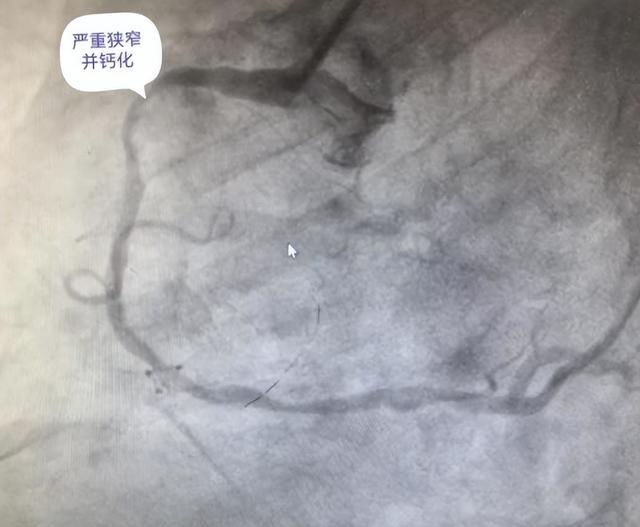

贺大爷近半年来反复出现胸痛症状,近期疼痛加剧便前来该院心血管内科就诊。冠脉造影显示其右冠状动脉严重狭窄伴弥漫性钙化,血管内壁如同被浇筑了“混凝土”。这种钙化病变硬度高,传统介入器械难以突破,且易引发血管撕裂等严重并发症。

【术前冠脉造影】